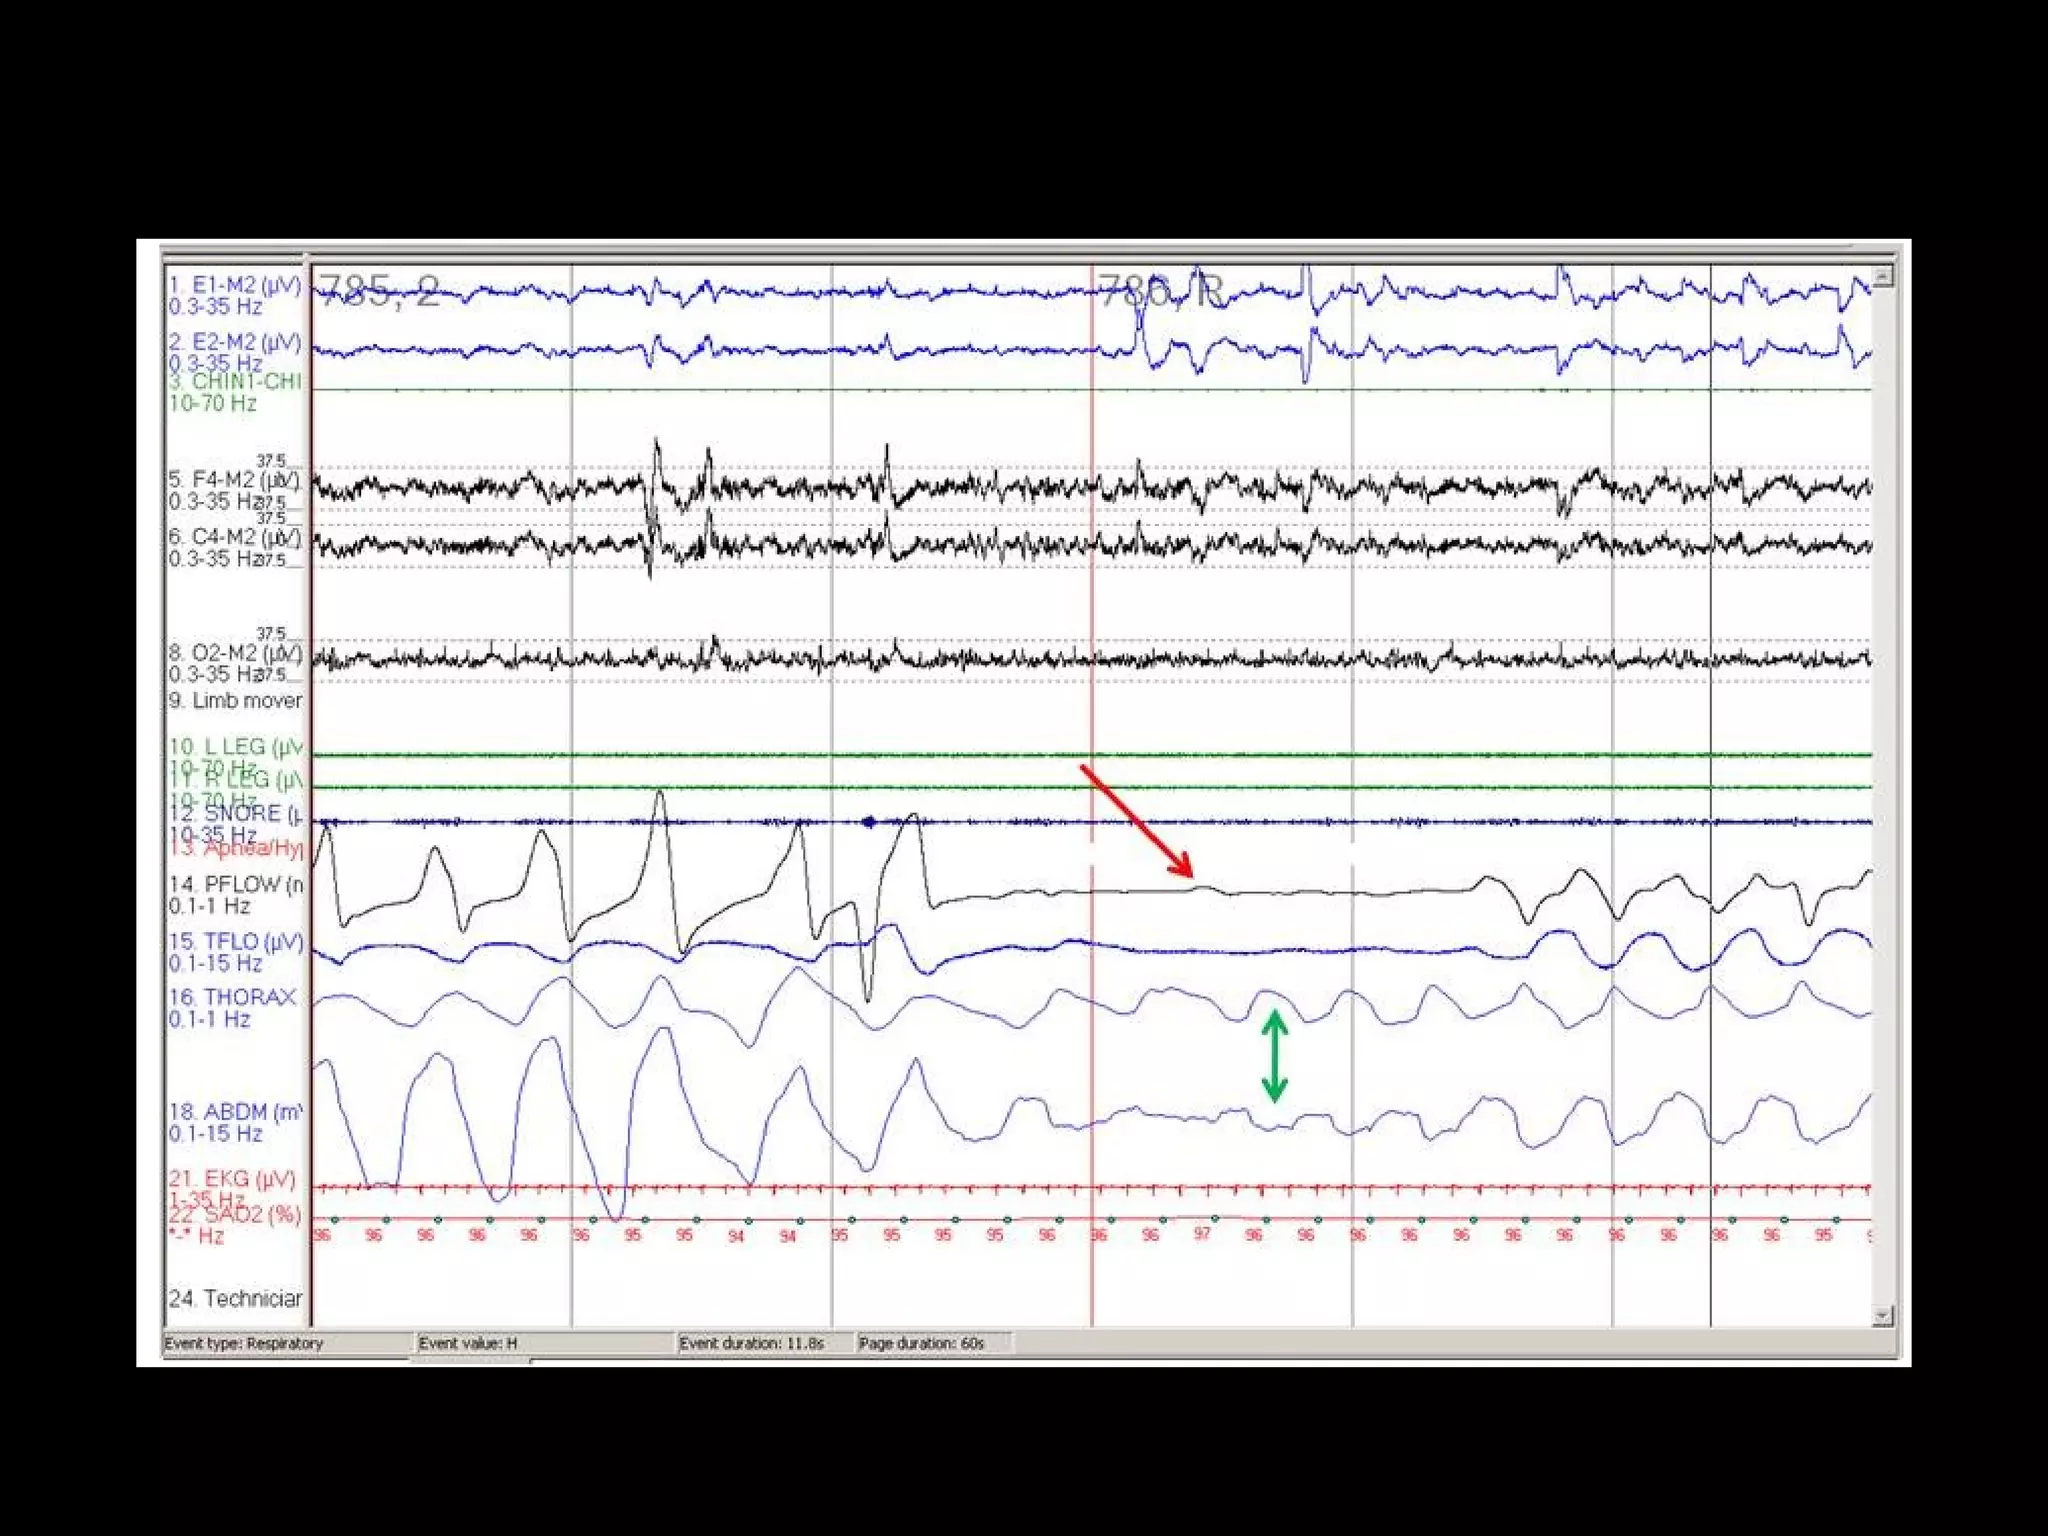

#46 Mixed sleep apnea. Note that the apnea (orange arrow) begins as a central apnea (effort absent; red double arrow) and ends as an obstructive apnea (effort present; green double arrow). Note the arousal (blue arrow) that terminates the apnea and the desaturation (purple arrow) that follows

#45 Central sleep apnea (thick areas). Note the absence of both flow and respiratory effort (green double arrows).

Central apnea is the cessation of airflow for at least 10 seconds with no respiratory effort